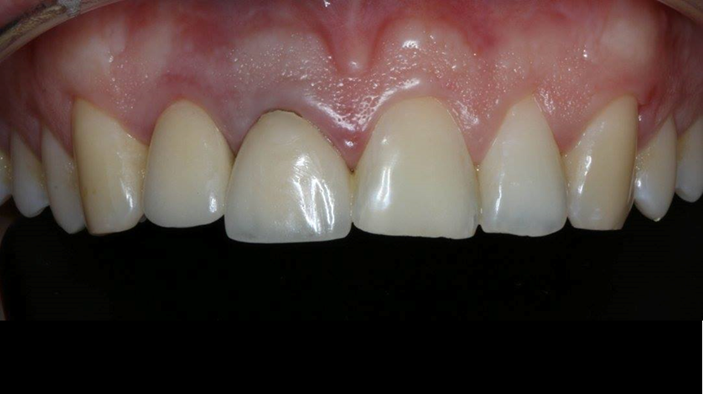

Clinical case: Patient-centered approach: treatment strategy for Root Membrane Technique & delayed implant placement

- Courtesy of Dr. Yoshiharu Hayashi, Japan -

Socket Shield Technique, anterior esthetics, maxillary anterior, esthetic, esthetics, delayed implant placement, socket preservation, AnyRidge, Root Membrane Kit, Root Membrane Technique, Partial Extraction Therapy, PET, esthetic zone, fuse abutment, Dr. Yoshiharu Hayashi,#11,#21,#22

Products:

AnyRidge implant system, fuse abutment Root membrane kit, PET Kit